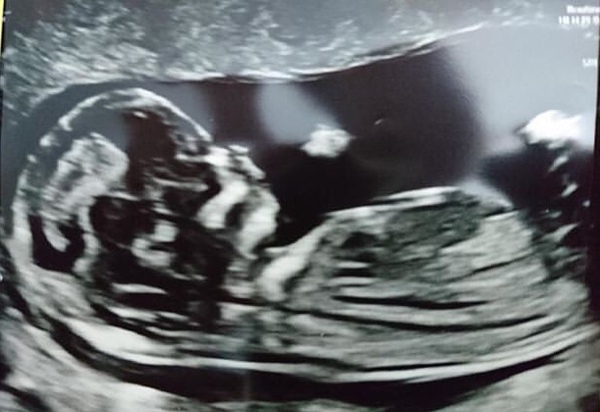

Attached scan, looked like a boy at the time but now I’m wondering...what do you all think?